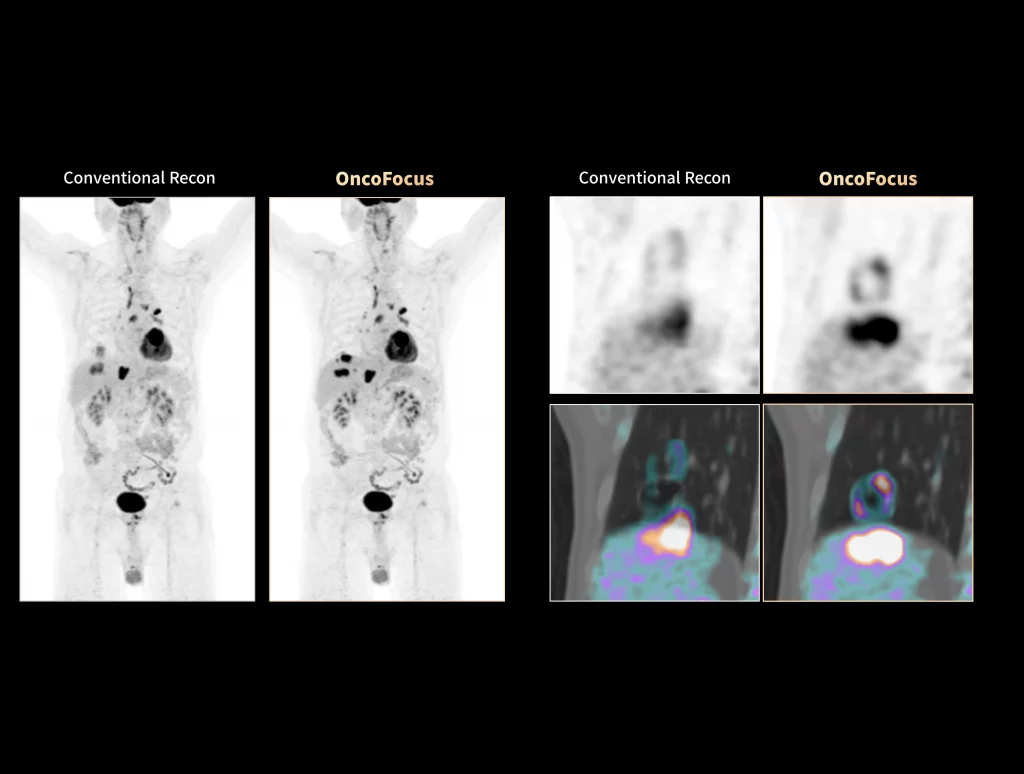

uMI Panorama is greatly empowered by innovative technologies integrated into the uExcel SCAN and uExcel CARE workflows. With uExcel SCAN, you can rely on intelligent positioning, scanning, and motion correction to streamline your routine tasks and maximinze your work efficiency. And uExcel CARE features uExcel DPR and uExcel AIIR reconstruction algorithms to ensure clear images even at low doses.

With the ultra-high system performance, uMI Panorama faces up to the challenges of tracers with different half lives and the complex scanning conditions, without compromise for image quality.